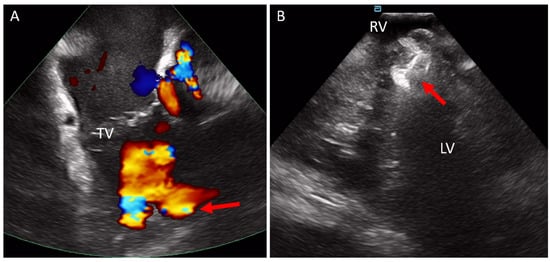

5.3. Transcatheter Pulmonary Valve Replacement (TCPVR)